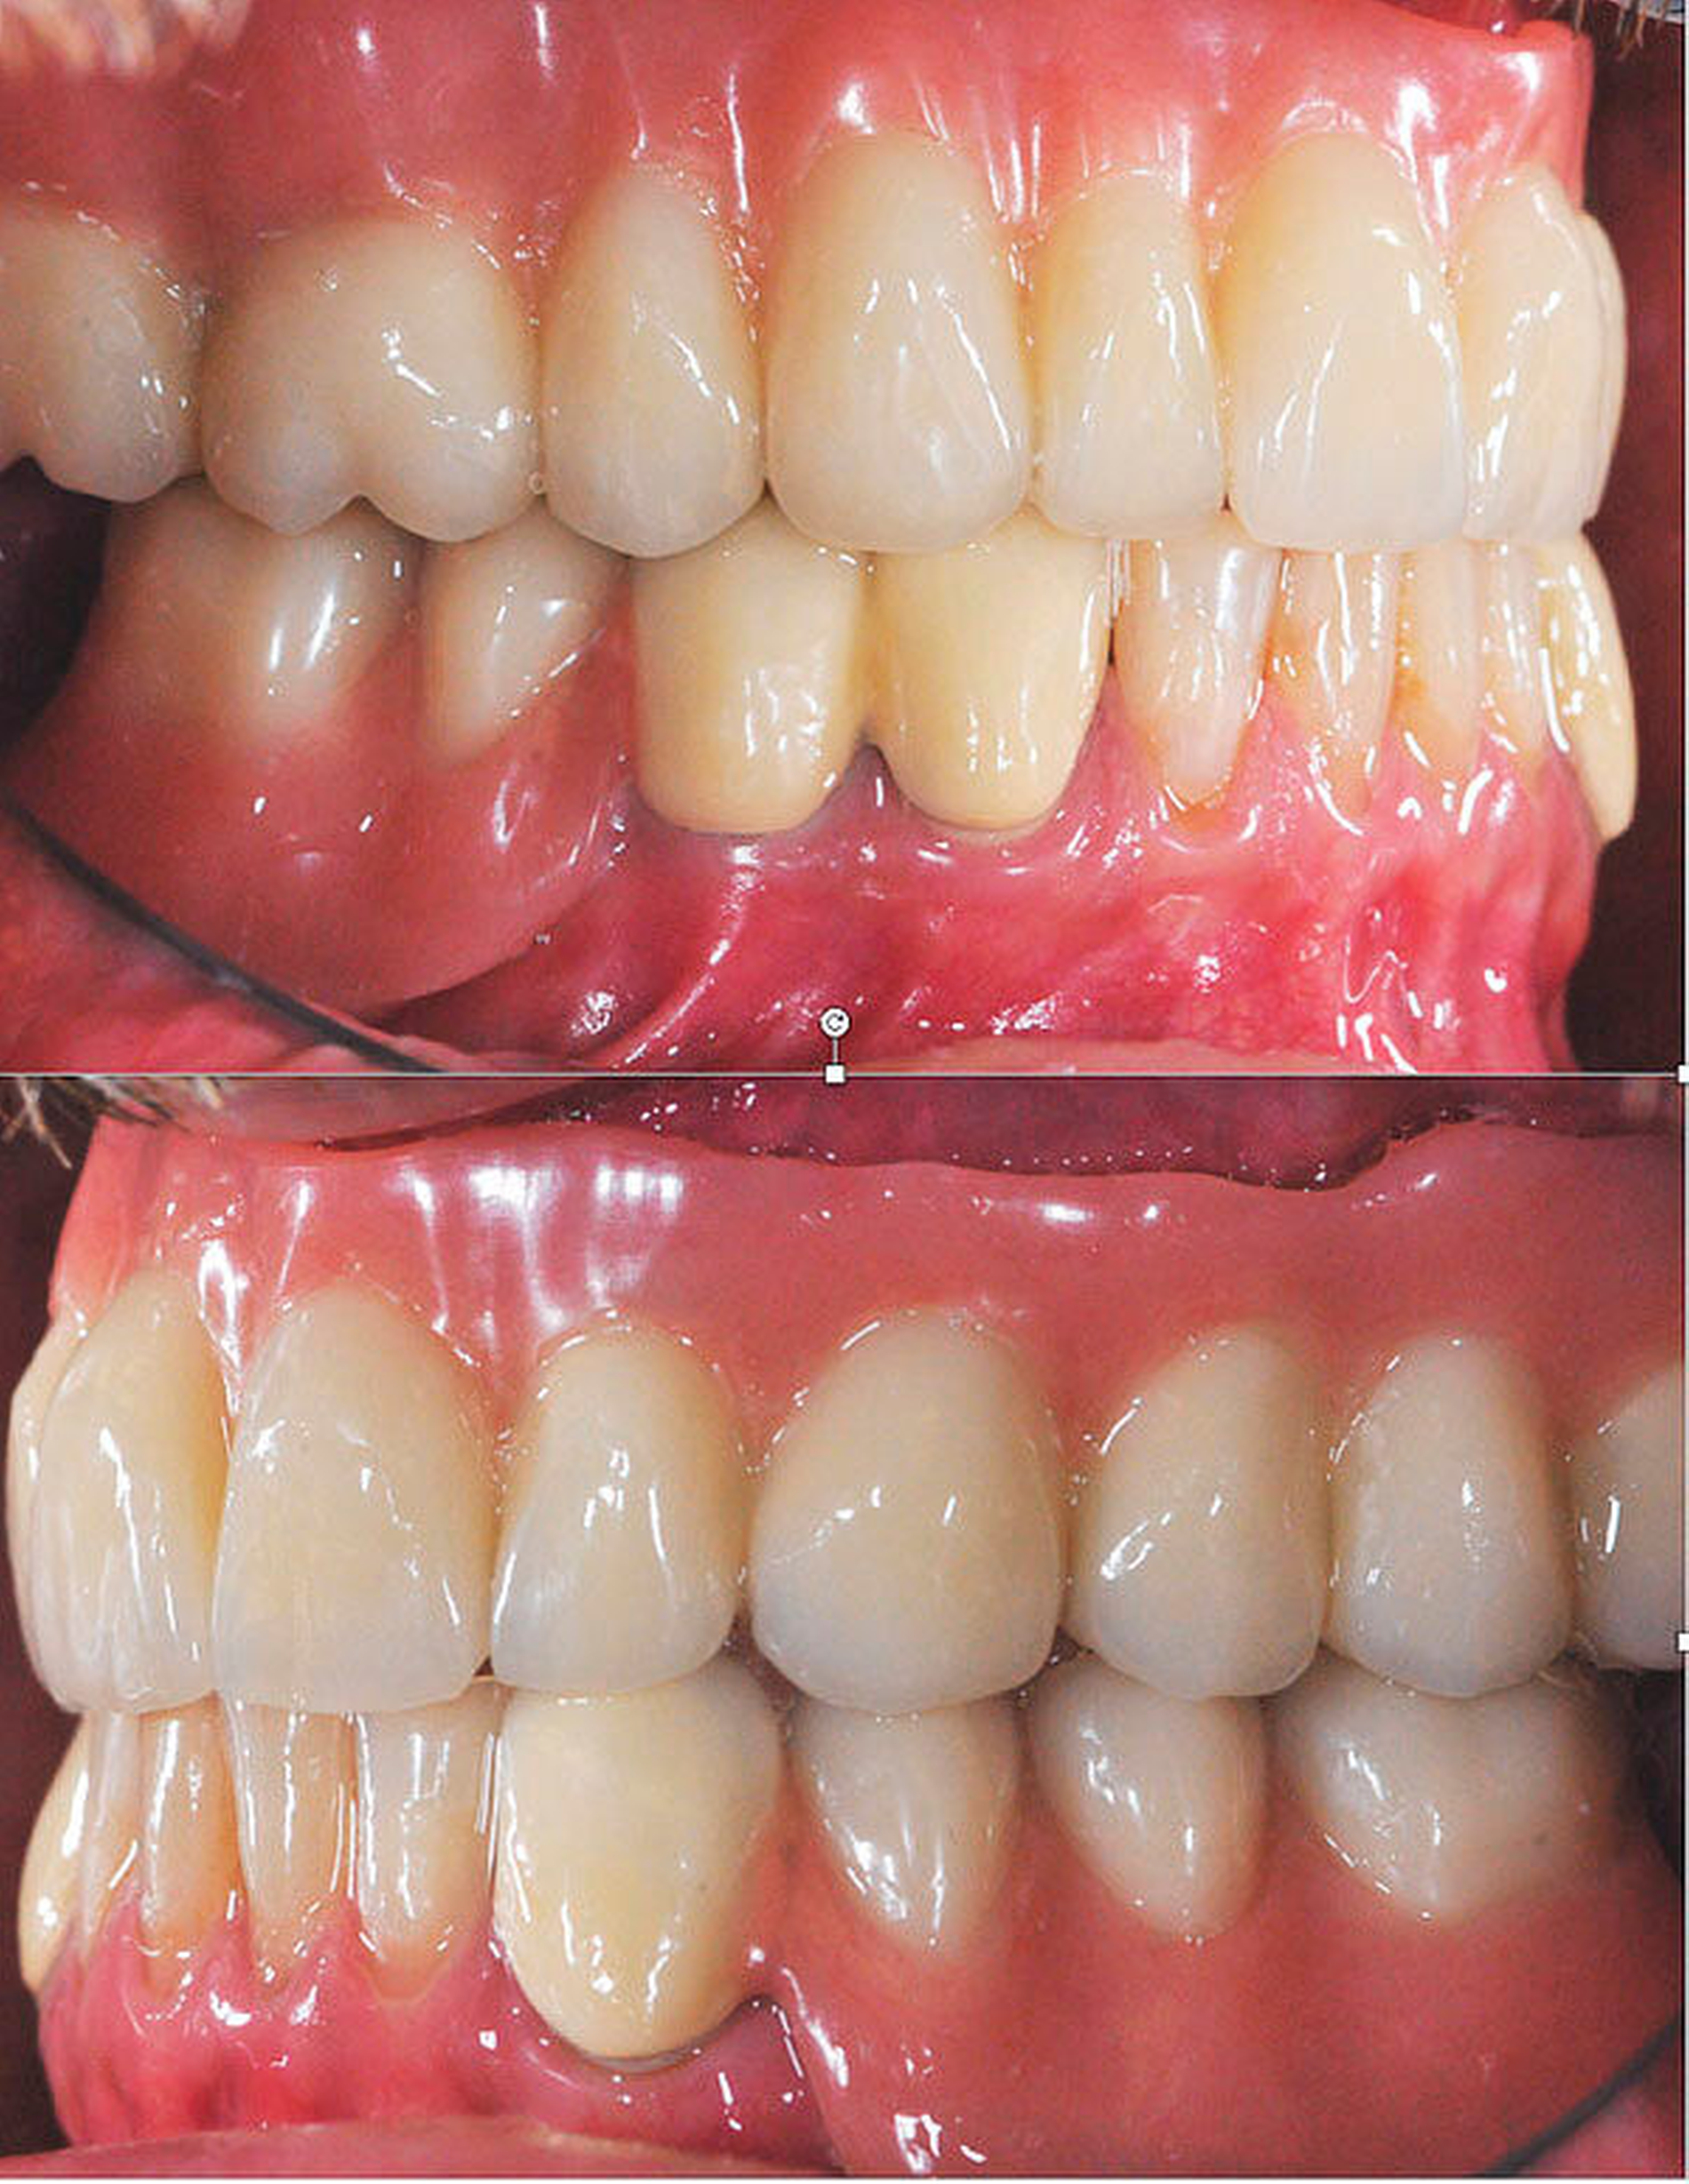

Nach unauffälliger Heilung ohne Komplikationen und Korrektur der Kieferrelation (Abbildung 5) konnte die definitive Versorgung (CARES®; Straumann, Basel, Schweiz; Sinfony®, 3M ESPE, Seefeld, Deutschland) drei Monate später eingegliedert werden (Abbildung 6). Im Rahmen der Nachsorgeuntersuchungen (Follow-up aktuell: 2,5 Jahre) zeigten sich stabile Okklusionsverhältnisse bei reizlosem Lokalbefund.